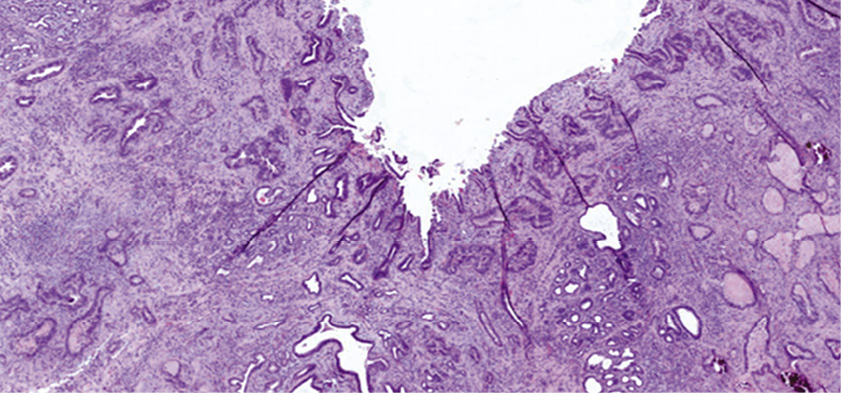

Изучение геномного профиля больных с холангиокарциномой позволило установить наличие мутаций гена ERBB2. H. Lee и соавт. в своем исследовании изучили 99 образцов, при анализе которых, кроме того, выявлены мутации генов KRAS, PTEN; ATM и NF1 и CCND1, FBXW7, GNAS, MDM2 и NRAS [12]. Суммарно мутации выявлены у 82 (83%) больных с внепеченочной холангиокарциномой. Значительно реже выявлялись мутации в генах BRAF, BRCA2, CDK4, CDK6, FGFR1, FGFR3, PTCH1, RAF1 и STK11, а мутаций в генах IDH1 и IDH2 не выявлено вовсе. На рис. 1 представлена гистологическая картина умеренно дифференцированной аденокарциномы желчного протока с мутацией ERBB2 S310F. Известно, что мутации внеклеточного домена ERBB2 реагируют на таргетную анти-HER2-терапию, что означает возможность ее использования в лечении таких пациентов. Применение двойной блокады HER2 пертузумабом и трастузумабом пока не входит в клинические рекомендации, одобренные Минздравом России, но, как считают многие исследователи, может быть рекомендовано в качестве 2-й и последующих линий терапии.

Рис. 1. Внепеченочная холангиокарцинома с мутацией ERBB2 S310F. Окраска гематоксилин-эозином [12].